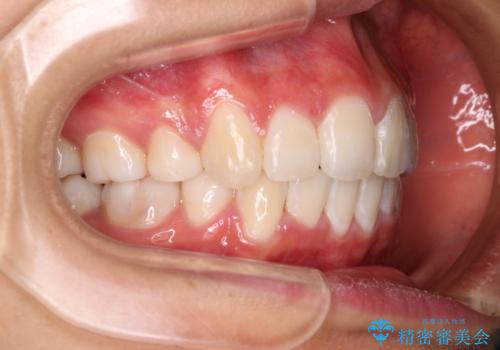

- 出っ歯とデコボコを気にして来院された患者様です。

口元の突出感を改善するため、上下左右第一小臼歯4本の抜歯を行い、ワイヤー装置による矯正治療を行うこととしました。

治療前の上下正中はずれていましたが、骨格的な上下左右差はあまり認められなかったため、正中を揃えて治療を終えることができました。

1年半ほどで治療を終えることができるとは我々も想像しておらず、患者様には大変満足していただきました。